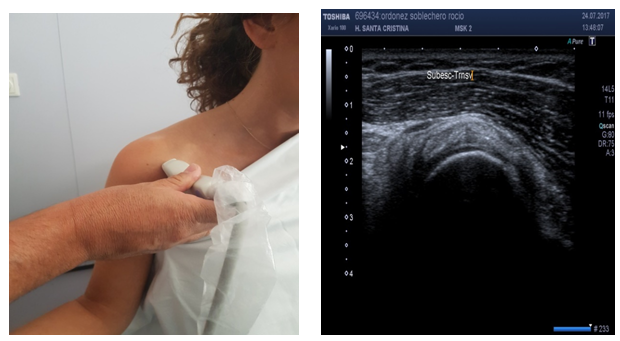

Subscapularis tendon (short axis) (Figure 5)

Patient position: Patient is seated, arm at side, elbow flexed, arm externally rotated with palm up (supination).

Probe position: Probe over anterior deltoid, axial to upper arm, short axis view.

Scan of structures: Because of the orientation of fibers, short axis depicts the insertion of tendon on lesser tuberosity and it is seen as beak-shaped.17,18

Subscapularis tendon (long axis) (Figure 6)

Probe position: Probe over anterior deltoid, longitudinal to upper arm, long axis view.

Scan of structures: Because of the orientation of fibers, longitudinal view is actually a transverse view of the muscle´s tendon. Three or four bright tendon fiber bundles may be seen on this scanning. Do not interpret as rupture or tears on subscapular tendon.17,18

Figure 5 Sonoanatomy of the subscapularis tendon (short axis).

Figure 6 Sonoanatomy of the subscapularis tendon (long axis).

US is the most difficult technique to perform by radiologists. US is operator dependent. The learning curve is time consuming. Specific operative knowledge on Knobology (knowledge of US equipment), sonoanatomy, patient’s and probe’s position are required.8 On evaluation of images, radiographies and magnetic resonance imaging have an anatomical representation. On the contrary, US images are harder to understand.8 The position of the patient may favor the exposition of anatomical structures, especially on shoulder evaluation (Figure 1). When evaluating an anatomical structure, the probe on long axis position (longitudinal evaluation) is quite different than the probe on short axis position (transversal evaluation).

Figure 1 (A) The position of the shoulder may favor the exposition of anatomical structures. Supraspinatus tendon is better exposed on the “Marilyn Monroe pose”, (B) while supraspinatus tendon is better exposed on the “military position”.